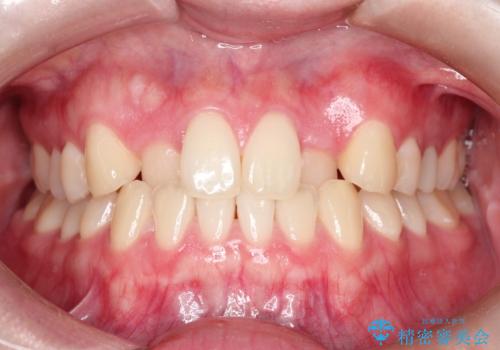

- 前歯のガタツキが気になるとのことで来院されました。

ワイヤー矯正とインビザライン矯正を併用することによって、治療期間の短縮と、より良い仕上がりを目指す治療を選択することとしました。

インビザライン(アライナー)矯正とワイヤー矯正のそれぞれの利点を生かした治療を行い、綺麗な歯並びになりました。